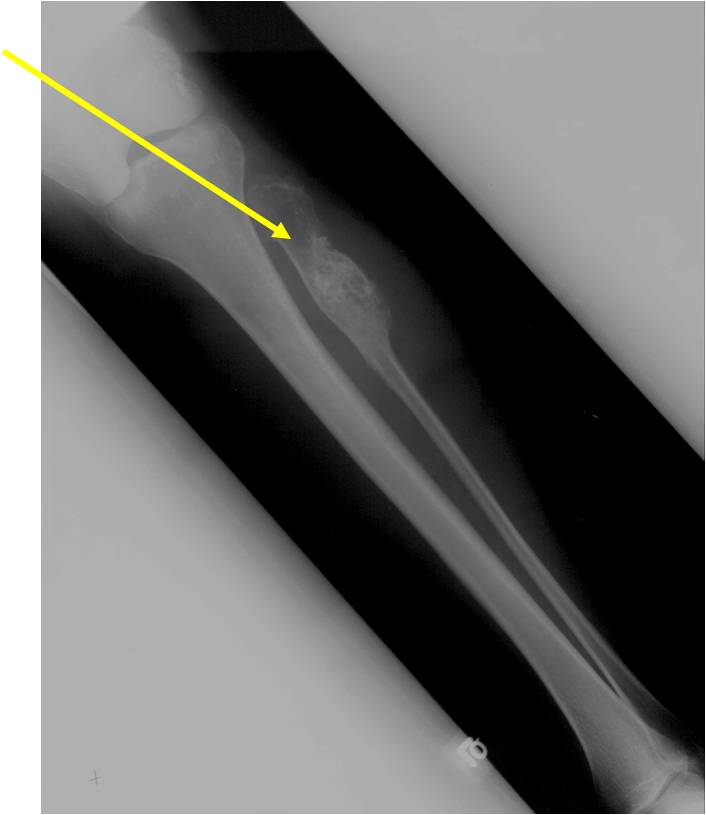

Metaphyseal Tumor Heavy Calcifications Ring and Arc Pattern of Calcifications Minimal Endosteal Scalloping No Cortical Destruction No Periosteal Reaction No Cortical Destruction No Soft Tissue Component

Geographic Lesion Bony Expansion Minimal Calcification Some Enchondromas do not calcify